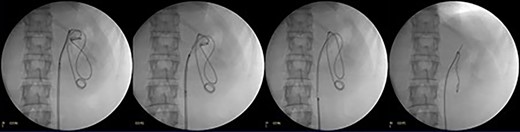

Endoscopic exploration revealing the tip of a subcapsular renal DJ stent intraparenchymal just behind the renal papilla, managed by using N-Gage from (Cook) in order to confront-capture the DJ stent tip. (A) Tip of a DJ stent intraparenchymal. (B and C) N-Gage basket capturing the tip of a DJ stent.

Patient underwent under general anesthesia. Cystoscopy was done, after that two guide wires, one for safety and the other one for ureteric access sheath were inserted under fluoroscopic guidance. Ureteral access sheath (UAS) was used to reduce the intrarenal pressure and by that we aimed to reduce the extravasation. Ureter was intact on retrograde pyelogram with no extravasation. A 35-cm 10/12F ureteric access sheath was passed over the guide wire and nephroscopy started. The endoscopic exploration revealed that the tip of subcapsular renal DJ stent was intraparenchymal just behind the renal papilla; therefore, we used N-gage from Cook in order to confront-capture the DJ stent tip [Fig. 2]. DJ stent was removed smoothly as shown in fluoroscopy [Fig. 3]. Patient was discharged in day one postoperatively. Patient was doing fine till we saw her 6 weeks postremoval of DJ stent not complaining of any symptoms except small perinephric collection on renal ultrasound. That collection completely disappeared in 6 months of follow-up.